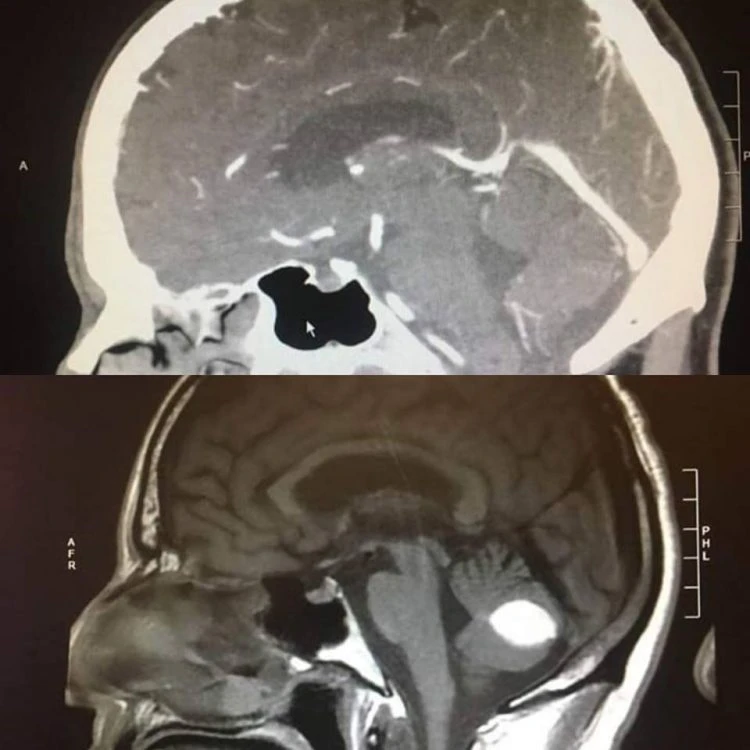

Phim chụp CT trước và sau cho thấy khối u não của ông Paul biến mất kỳ lạ. Ảnh: Facebook

Ông Paul Wood, sống ở Lodi, California bắt đầu bị những cơn đau đầu kinh khủng hành hạ vài tháng trước. Sau khi làm các xét nghiêm, các bác sĩ giải phẫu thần kinh tại BV UC San Francisco nói rằng ông bị xuất huyết não, đồng thời phim chụp CT cho thấy có một khối u trong não và ông Paul cần phải phẫu thuật sớm để không ảnh hưởng đến tính mạng.

Tuy nhiên, đến trước hôm dự kiến phẫu thuật một ngày, phim chụp CT mới cho thấy khối u đã tự nhiên biến mất một cách kỳ diệu mà không một bác sĩ nào lý giải được nguyên nhân.